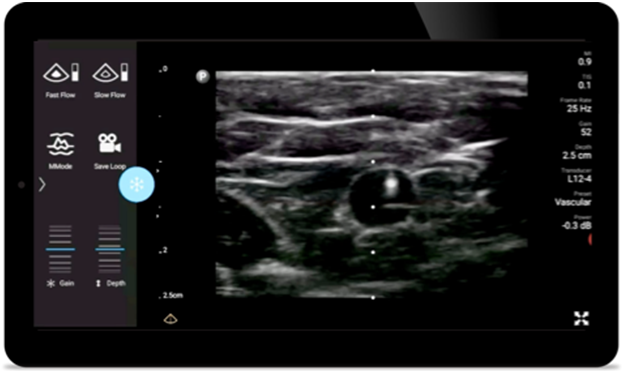

Lumify helps you clearly visualize needle placement, surrounding nerves, vessels and fascial planes.

Lumify transducers for anesthesiology

Broadband linear array transducer

Lumify L12-4 broadband linear array transducer

• 12 to 4 MHz extended operating frequency range

• Aperture size: 34mm

• 2D, steerable color Doppler, M-mode, advancedXRES and multivariate harmonic imaging, SonoCT

• High resolution imaging for shallow applications: soft tissue, vascular, superficial, musculoskeletal and lung

• Center line marker

• USB-C transducer with replaceable cable